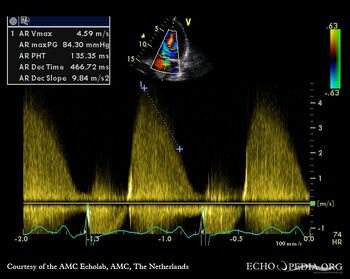

E00183.gif

E00184.jpg

A5CH: Color Doppler signal of severe aortic regurgitation Continuous-wave Doppler signal of severe aortic regurgitation, PHT 135 msec